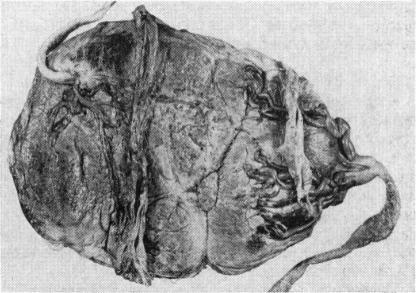

The Placental Transfusion Syndrome in Monozygous Twins.

Arch Dis Child. 1965 Jun;40(211):264-70. doi: 10.1136/adc.40.211.264.